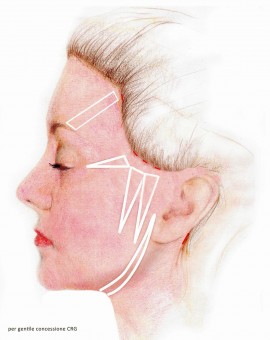

A livello delle ascelle, in sostituzione alla tossina botulinica, può essere impiegato l’innovativo trattamento con il laser.

In anestesia locale, attraverso una piccolissima incisione che non necessita nemmeno di punti di chiusura, si introduce a livello ascellare la fibra laser del diametro di 0,6 mm. che provoca lo scioglimento del tessuto sottocutaneo all’interno del quale sono contenute la ghiandole sudoripare, provocandone la loro distruzione in maniera definitiva e permanente.

Per chi desidera quindi risolvere in maniera efficace e durevole il problema dell’iperidrosi ascellare, il trattamento con endolaser a diodo rappresenta la soluzione vincente.